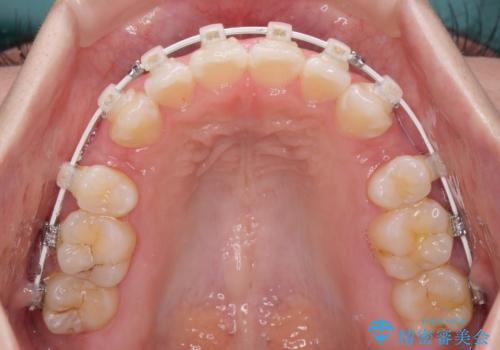

- 矯正装置

- 審美装置

- 1年11ヶ月

上下左右第一小臼歯4本を抜歯し、ワイヤー装置にて口元を引っ込めるよう矯正治療を行うこととしました。